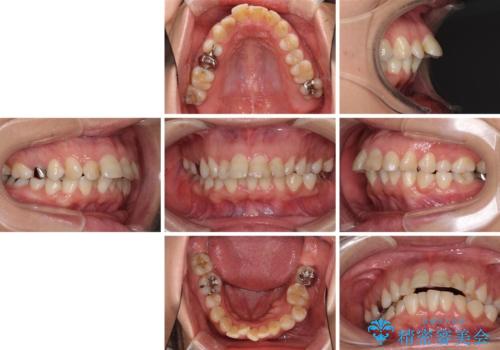

- 前歯のデコボコと前方に斜めに飛び出した前歯を気にして来院された患者様です。

口元の突出感はあまり気になっていませんでしたが、上下の前歯の前後差が大きかったため、上顎左右の第一小臼歯を抜歯し、上顎が裏側装置であるハーフリンガルにて矯正治療を行うこととしました。

途中で、下顎の小臼歯を抜歯する必要があれば、再度診断を行っていくこととしました。